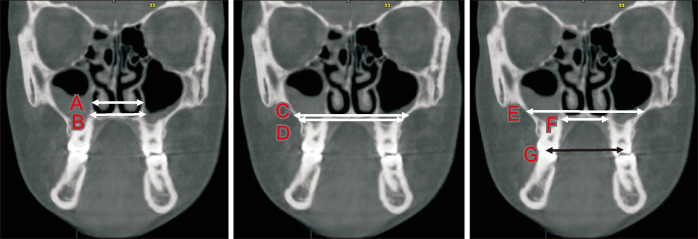

Methods: Pretreatment and post-expansion cone beam computed tomography scans of 30 patients (mean age: 18.6 years), diagnosed with maxillary transverse deficiency, were grouped into three (n = 10 each) according to expansion protocol: 1) MARPE; 2) SARME without PD [SARME-PD(-)]; 3) SARME with PD [SARME-PD(+)]. In NemoStudio software, eleven linear measurements were used to evaluate nasal and maxillary skeletal parameters. Eight airway measurements were used to evaluate the volume and minimum cross-section of the nasal cavity, nasopharynx, retropalatal region, and retroglossal region. Intragroup and intergroup changes were evaluated for statistical significance at P < 0.05.

Results: Nasal lateral, nasal floor, external maxillary, palatal, and maxillary intermolar widths significantly increased in all groups. In MARPE, nasal cavity and nasopharynx volumes and minimum cross-sectional area increased significantly. Nasopharyngeal volume increased significantly in SARME-PD(-), whereas nasal cavity volume and minimum cross-sectional area decreased significantly in SARME-PD(+). MARPE group showed greater expansion in nasal lateral width than SARME-PD(-) and SARME-PD(+) groups. Mean changes in nasal cavity volume, minimum cross-sectional area, and nasopharyngeal volume were significantly greater in MARPE than in SARME-PD(+).